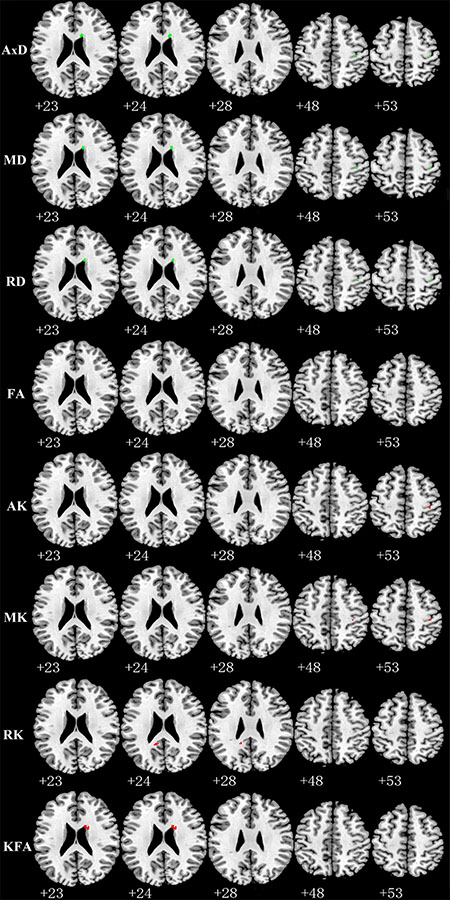

Compared with TT homozygotes, KIBRA C-allele carriers showed increased AxD (axial diffusivity), MD (mean diffusivity), RD (radial diffusivity), decreased AK and MK in right postcentral gyrus WM. And we found increased AD, MD, RD and decreased KFA (kurtosis fractional anisotropy) in right periventricular WM in KIBRA C-allele carriers. (Figure 1). The results are listed in Table 2.

Figure 1: Representative axial images show differences in WM (p < 0.001, with a minimum cluster size 10) between TT carriers and C carriers for all indices: AxD, MD, RD, FA, AK, MK, RK and KFA. Green and red represents the clusters with increased and decreased indices in KIBRA C-allele carriers compared with TT carriers, respectively. FA showed no difference between the two groups. Abbreviation: AxD: axial diffusivity; MD: mean diffusivity; RD: radial diffusivity; FA: fractional anisotropy; AK: axial kurtosis; MK: mean kurtosis; RK: radial kurtosis; KFA: kurtosis fractional anisotropy.